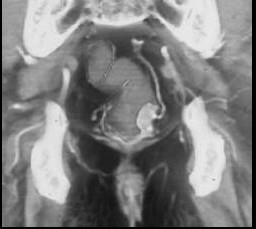

男,50岁,血便,大便形状改变,CT如图,应考虑为 ( )A、直肠腺瘤B、直肠淋巴瘤C、直肠内粪便D、直肠癌E、直肠息肉

问题 男,50岁,血便,大便形状改变,CT如图,应考虑为 ( )

选项 A、直肠腺瘤 B、直肠淋巴瘤 C、直肠内粪便 D、直肠癌 E、直肠息肉

答案 D